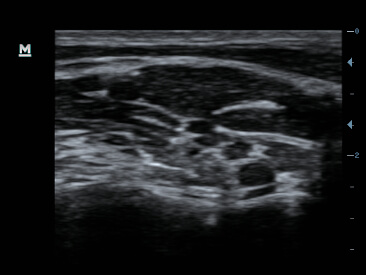

Clinical Images